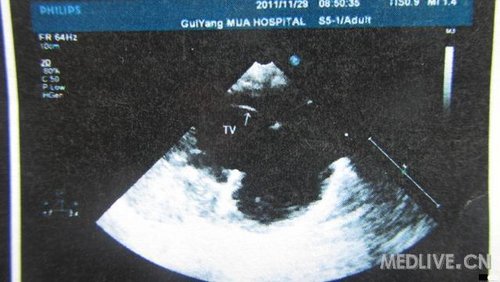

患儿,女,6月,足月剖腹产,出生后家长发现喘憋,未重视。现症状加重,不能喂食而就诊!

片子列出,急盼高手指点,不知生存几率有几分?